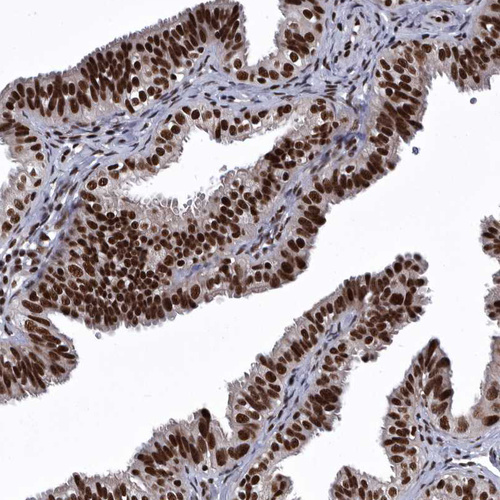

Immunohistochemical staining of human endometrium shows strong nuclear positivity in glandular cells.